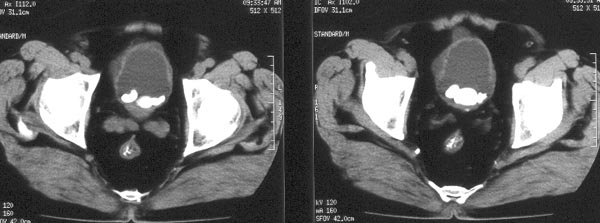

男性,74岁。尿频、尿线变细2年余,去年曾在外院膀胱结石超声碎石术。

ct平扫:膀胱内尿液充盈欠佳,膀胱壁较厚,前部见囊水样低密度影,内可见两枚直径1cm左右的钙化结石排列成串。膀胱右侧壁亦见囊水样低密度影。膀胱内可见多枚钙化密度结石影排列成串,大小约4.5x2cm。

ct诊断:1、膀胱多发结石。2、膀胱多发憩室,并憩室内多发结石。